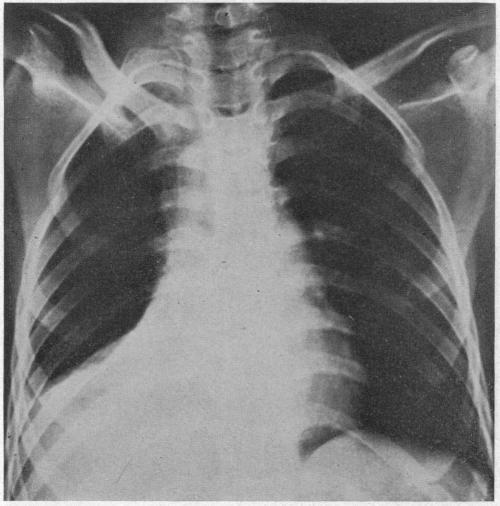

ACUTE MASSIVE COLLAPSE OF THE LUNGS: A DISCUSSION OF ITS MECHANISM AND OF ITS RELATION TO FOREIGN BODIES IN THE BRONCHI AND POST-OPERATIVE COMPLICATIONS.

摘要